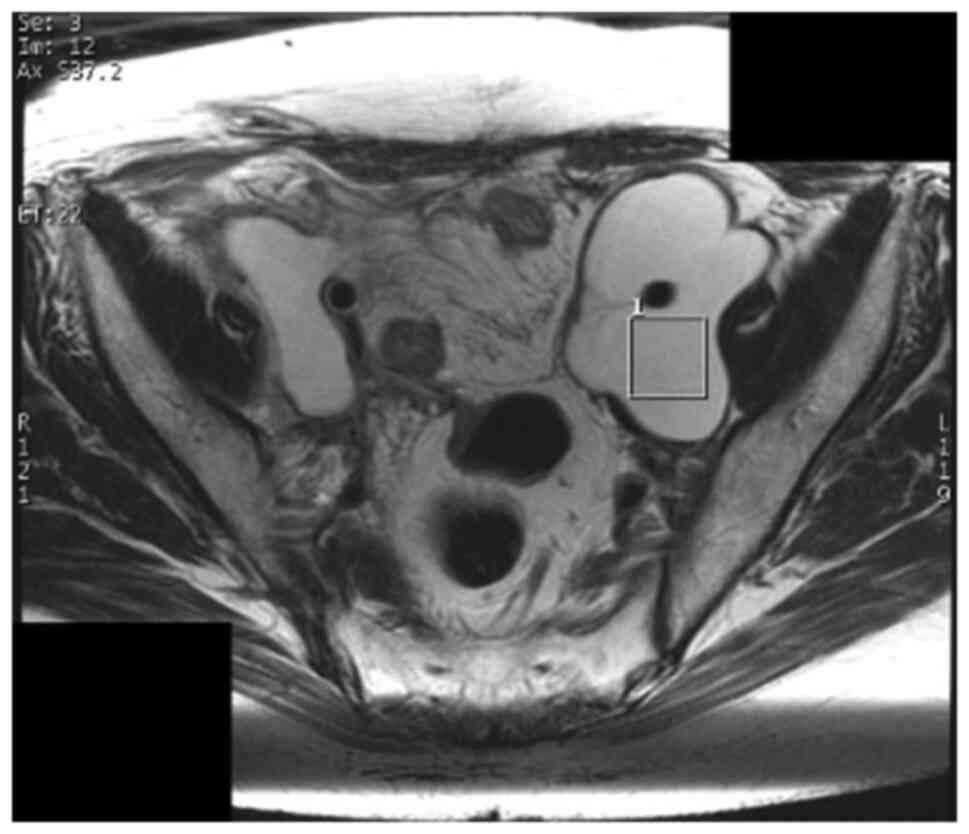

MRI and MRS were performed with a 3T clinical scanner equipped with a 32-channel body coil (Discovery MR750 3.0T, GE Healthcare, Waukesha, WI). Before MRS, routine clinical MRI was performed, including collection of fast spin echo (FSE) T2-weighted images (T2WI) in the axial and sagittal planes (TR/TE=4,000/100 msec), FSE T1-weighted images (T1WI, TR/TE=500/6 msec), and axial diffusion-weighted images (DWI, TR/TE=6,000/60 msec, b=0 and 1,500 s/mm2). MRS was performed before surgery or drainage using a point-resolved spectroscopic sequence (PRESS) (TR/TE=2,000/144 msec, spectral width=2,500 Hz, number of points=2,048, total number of scans=96) with an automated shimming method. A region of interest (ROI) for data acquisition of size 20x20x20 mm3 was placed in the center of the abscess, with reference to previously obtained T2WIs in the axial and sagittal planes (Figs. 1 and 2). In general, lesions in the pelvis show little respiratory variability. To obtain signal intensity and to minimize errors, a cube with 20 mm long sides was set as ROI inside the abscess, which was considered to be a homogenous area, without including wall.